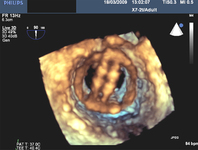

Mitral valve P2 leaflet prolapse: 3D view

From the collection of Prakash P. Punjabi